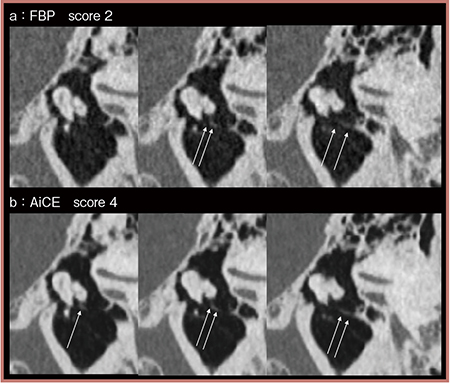

図4は鼓索神経の連続する画像の比較であるが,FBP(a)では左の画像で鼓索神経(→)を視認できないのに対し,AiCE(b)ではすべての画像で描出されており,スコア4と高い評価が得られた。

AiCE INNER EARによってノイズが除去されたことでCNRやSNRが上昇し,中内耳の微細構造の描出が改善した。手術によって損傷しやすい微細構造を明瞭に描出できるようになれば,合併症の頻度を低減できる可能性がある。

図4 AiCE INNER EARにおける中内耳の微細構造(鼓索神経)の描出の評価